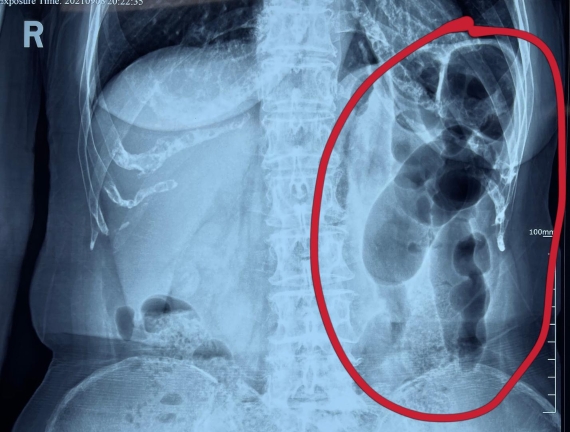

據(jù)省醫(yī)院消化病院消化二科姜子曄醫(yī)生介紹,韓大娘今年已經(jīng)73歲,家住哈爾濱市,一周前開始腹脹腹痛,有較為明顯的左側(cè)腹部疼痛,疼痛劇烈時會出現(xiàn)左側(cè)腹部鼓包情況,排氣排便后有所好轉(zhuǎn)。韓大娘家人見狀將其送到了黑龍江省醫(yī)院,門診檢查腹部平片提示為左側(cè)腹部積氣,口服全消化動力藥及通便治療后腹痛腹脹有所緩解,入院前再次突發(fā)左側(cè)腹痛加重伴有明顯腹脹,急診隨后以“腹痛腹脹原因待查”將韓大娘收入到消化病院消化二科。

姜子曄醫(yī)生熱情接待了韓大娘,為其進行了仔細查體,除了左側(cè)腹部壓痛并未見明顯異常,對癥給予灌腸后,韓大娘的腹脹有所緩解,第二天姜子曄醫(yī)生為韓女士進行了胃腸鏡檢查,也未見明顯異常。但此時韓大娘腹部平片結(jié)腸腸管擴張仍然很嚴重,腹痛腹痛也沒緩解,到底什么原因呢?消化二科主任陸以霞在查房時建議繼續(xù)給予韓大娘口服全消化動力藥,必要時灌腸治療,同時陸以霞主任在追問病史查體時發(fā)現(xiàn)韓大娘左下腹紅色皮疹和小水泡,反復(fù)抓撓腹部皮膚部分已結(jié)痂,高度懷疑為帶狀皰疹。